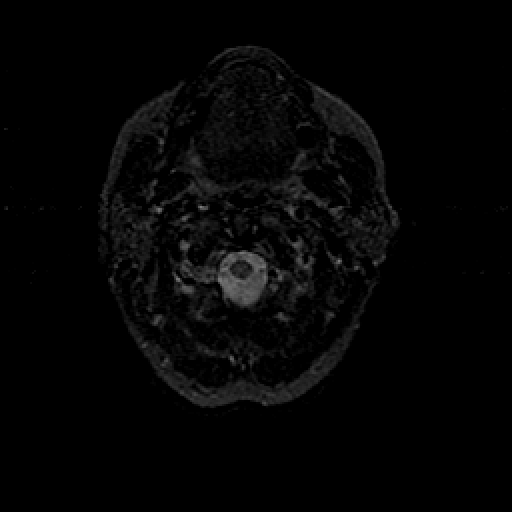

T2-weighted structural MR: Slice 2

Slice 2